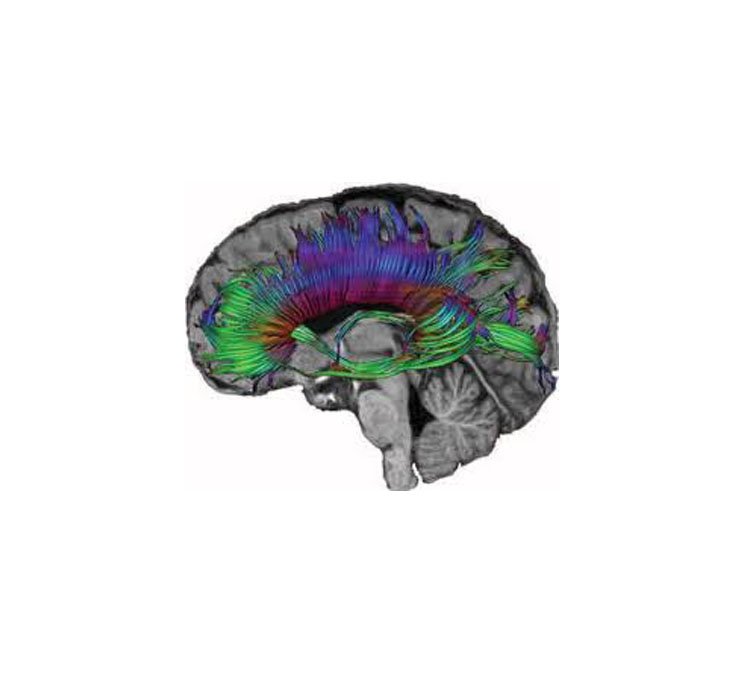

MR Tactography Brain

MRI Tactography